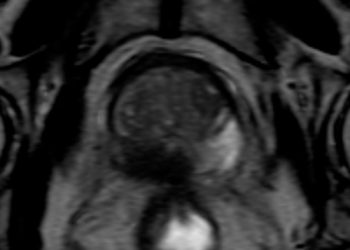

La resonancia magnética ha tomado un papel fundamental en el diagnóstico del cáncer de próstata, ya que nos permite confirmar o descartar la presencia de lesiones sospechosas en la próstata, disminuyendo así la cantidad de biopsias innecesarias y en los casos en que sea necesaria la biopsia aumenta su precisión diagnóstica. Cuando se confirma el diagnóstico de cáncer la resonancia también es de gran utilidad, ya que permite valorar la extensión de la enfermedad.

El diagnóstico definitivo de cáncer de próstata se obtiene mediante el analisis histopatológico del tejido extraído en una biopsia. La biopsia transrectal guiada por ultrasonido, técnica ampliamente utilizada desde la década de los 80`s es la mas conocida, sin embargo en la última década se han desarrollado nuevas técnicas con el objetivo de aumentar su precisión diagnóstica, una de estas es la biopsia prostática con fusión resonancia magnética-ultrasonido (MRI-TRUS) que permite sincronizar las imágenes obtenidas por resonancia magnética con las imágenes generadas por ultrasonido en tiempo real y dirigir la toma de muestras hacia las zonas de sospecha.